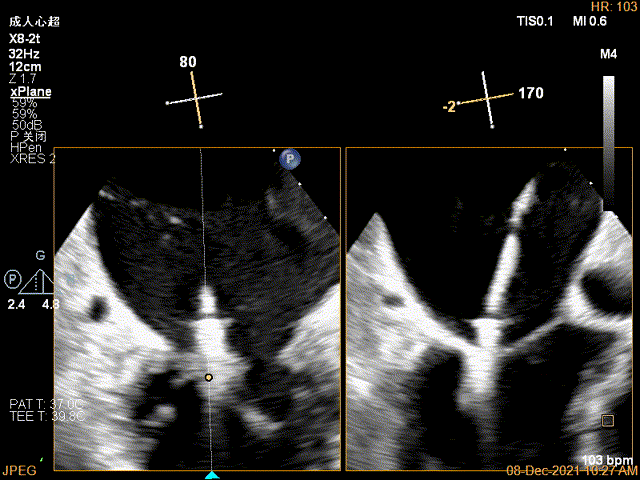

第一个夹子放置侯二尖瓣口平均跨瓣压差:4mmHg

肺静脉血流频谱恢复正向

x-plane验证前后叶抓捕后bond明显

3D-VIEW验证结果

3D-Color-view验证残余分流位于外侧